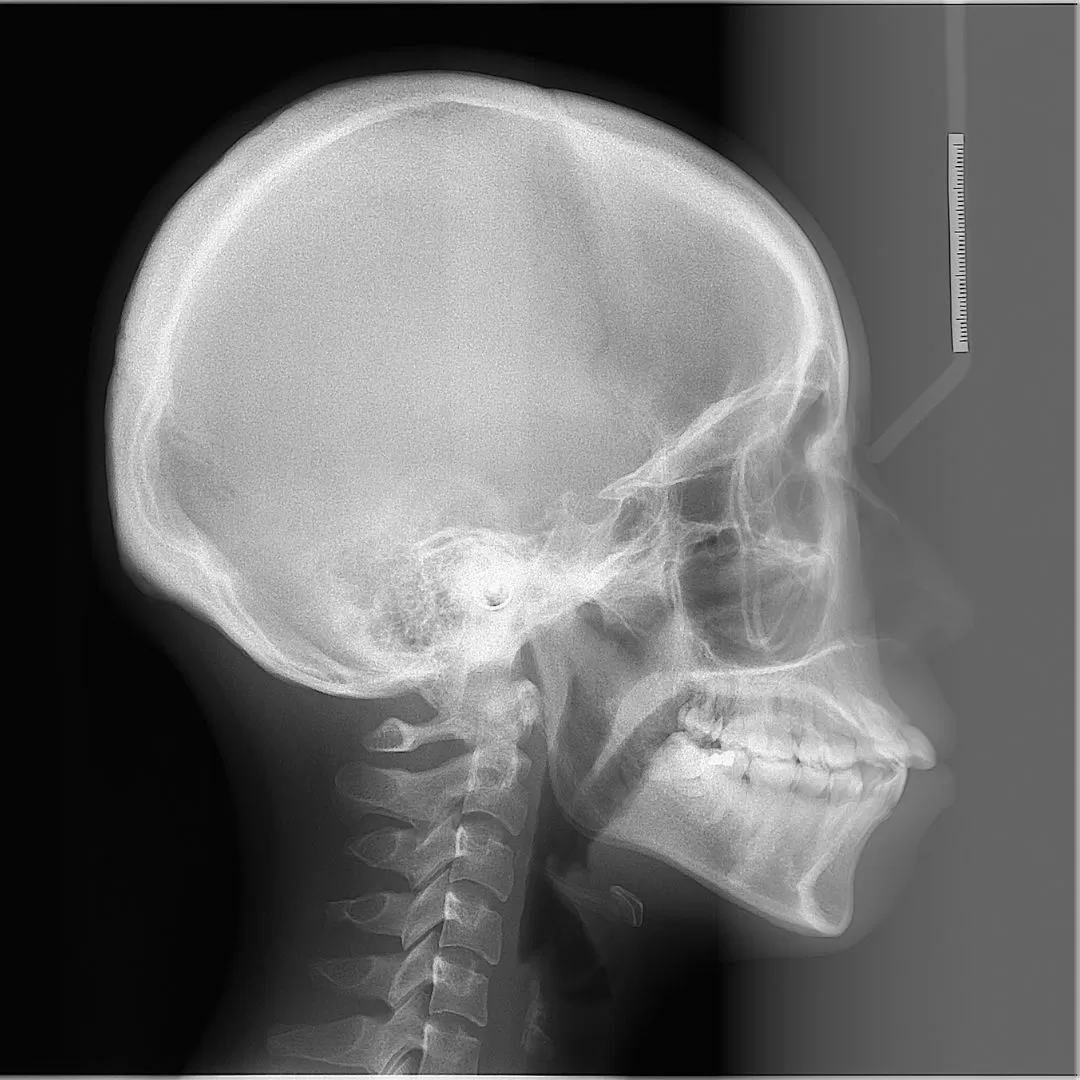

こちらをご覧ください。

かなりの前突と奥歯の噛み合わせの低下による、顎関節の圧迫が

見受けられる症例です。

術後を見てください。

前歯がひっこんだ!というのは短絡的です。

当然、顔面の変化はかなりあったでしょう。

奥歯の噛み合わせの上昇がみられていること、

また噛む位置の変化がおきていることで、顎関節の正常化も

見られているのです。

顎関節の正常化はお顔の歪みの正常化につながります。